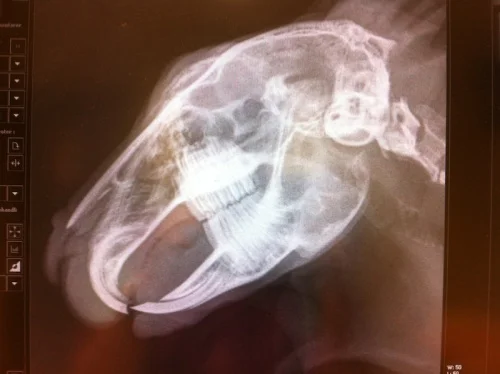

Røntgen av tenner for å få en fullverdig tannsjekk

Tannrøttene til baktennene til Serafina begynner å vokse ned mot kjevebenet. Framtennene møtes og dette skaper unormal vekst i baktennene og gir problemer med feil tannstilling.